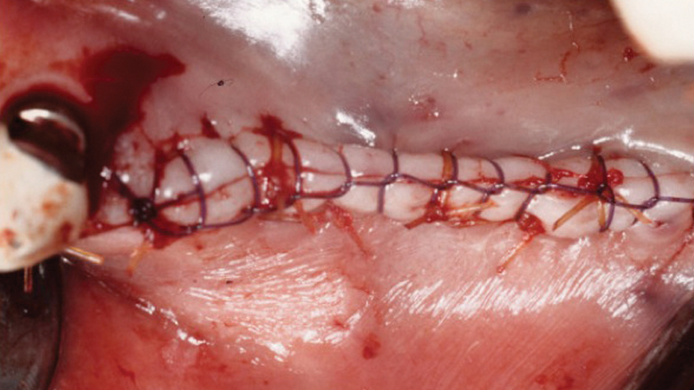

“Thin ridge expansion with minimally invasive surgery!

Use SmarThor & AnyRidge to place a wider diameter implant with minimal drilling after ridge splitting, even in thin ridge under 2mm! “

Clinical case: Ridge splitting technique using SmarThor + AnyRidge as expander

- Courtesy of Dr.Kwang-Bum Park, Korea -

Keywords

AnyRidge, ridge splitting, GBR, Dr. Kwang-Bum Park, mandibular posterior, SmartThor, Mega-Oss, thin ridge, bone regeneration

Products:

AnyRidge implant system. SmarThor, Mega-Oss